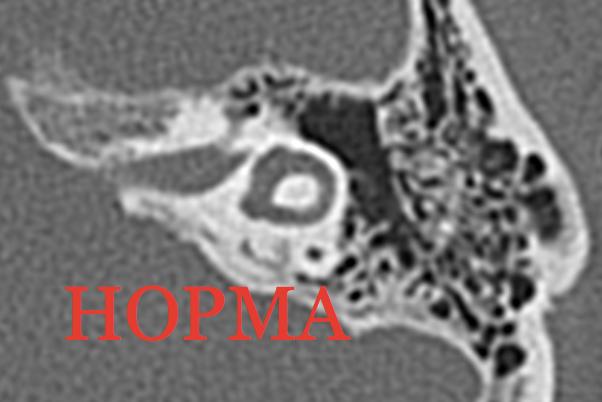

КТ анатомия сосцевидного отростка: особенности и показания

Раздел: Галерея прозрений